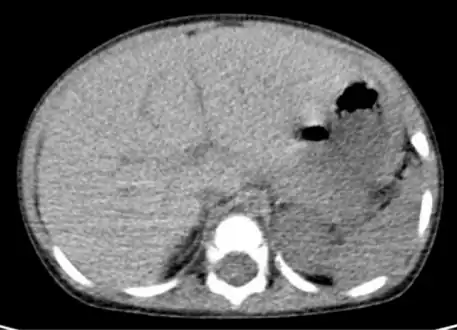

Computed tomography finding of hepatomegaly. -

Computerized tomography (CT) can help to obtain accurate anatomical information, in individuals with hepatomegaly for the purpose of a complete diagnosis.[21]